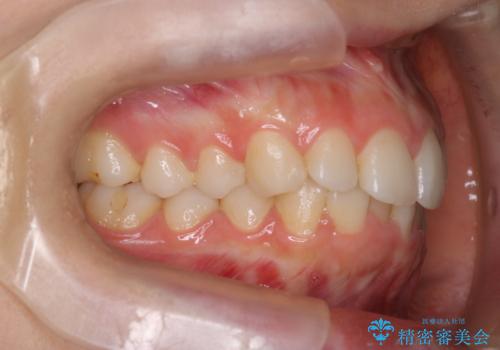

【インビザライン】前歯のガタガタをなおしたい。

- 前歯の凸凹を主訴に来院されました。

インビザラインにて奥歯の遠心移動を行いながら、前歯のガタガタを改善することができました。